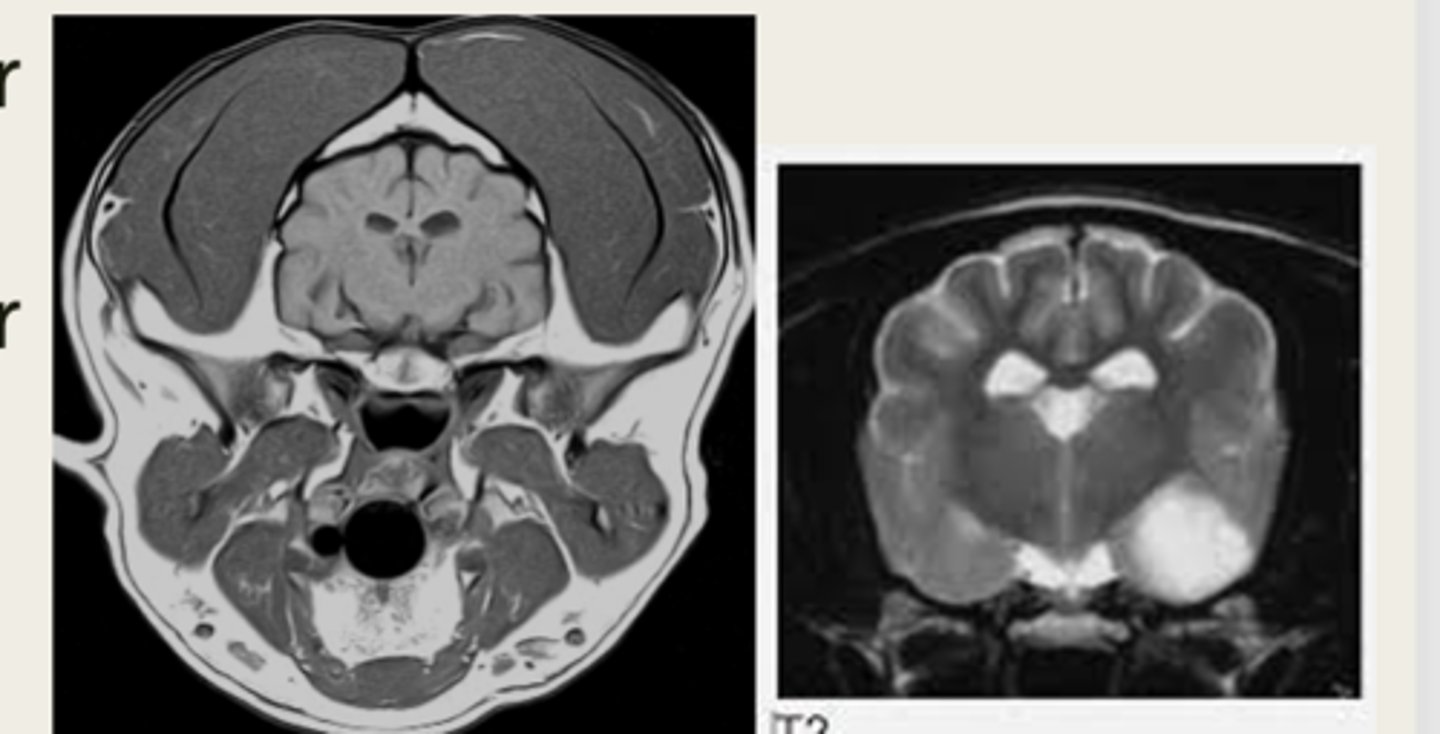

-T1 weighted

-T2 weighted

what are the two main MRI sequences?

left- T1 weighted

right- T2 weighted

which image is T1 weighted and which is T2 weighted?

anatomy

T1 weighted images are good for ________

pathology

T2 weighted images are good for identifying __________

hyperintense

Pathologic tissues such as tumors or areas of inflammation are "juicy" so they are what intensity?

left- T1 weighted

right- T2 weighted

which MRI image is T1 or T2 weighted?